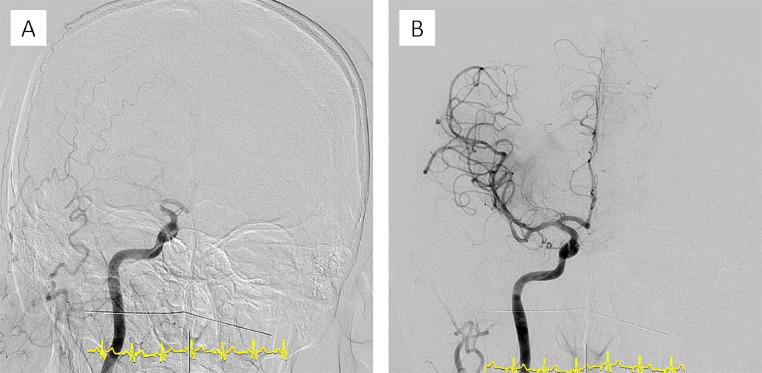

Situs inversus is a rare congenital abnormality characterized by mirror-image transposition of the major visceral organs and vessels. Few reports have discussed the use of mechanical thrombectomy in acute ischemic stroke with situs inversus. We present such a case, to raise awareness and deepen the knowledge on these cases. A 44-year-old man was admitted to our hospital with sudden-onset dysarthria and left-sided paresis. Computed tomography (CT) angiography revealed situs inversus and occlusion in the internal carotid artery. First, intravenous tissue plasminogen activator was administered, followed by immediate reperfusion with mechanical thrombectomy. We achieved thrombolysis in cerebral infarction grade 3. After the procedure, the patient fully recovered. Prompt diagnosis is crucial for rapid recanalization in patients with vascular anomalies such as situs inversus.

内脏反位是一种罕见的先天性异常,其特征为主要内脏器官和血管呈镜像转位。很少有报告讨论过在患有内脏反位的急性缺血性卒中患者中使用机械取栓术。我们报告了这样一例病例,以提高对这些病例的认识并加深了解。一名44岁男性因突发构音障碍和左侧肢体无力入住我院。计算机断层扫描(CT)血管造影显示内脏反位和颈内动脉闭塞。首先,给予静脉注射组织型纤溶酶原激活剂,随后立即进行机械取栓术实现再灌注。我们达到了脑梗死3级溶栓效果。术后,患者完全康复。对于患有诸如内脏反位等血管异常的患者,迅速诊断对于快速再通至关重要。